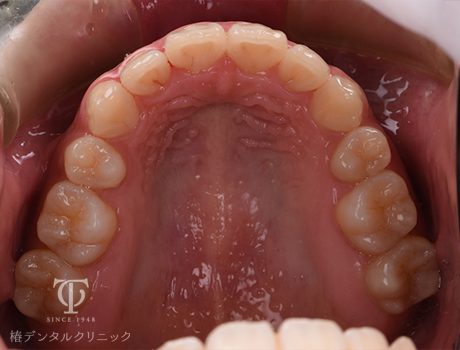

マウスピース装着後

Case01

-

- 症状

- 前歯の歯並びがずれてきた

- 治療期間

- 約5か月

- 治療費用

- 330,000円

以前全顎矯正をしていて後戻りをおこしてしまった患者様です。軽度の叢生のため、マウスピース矯正をおこないました。